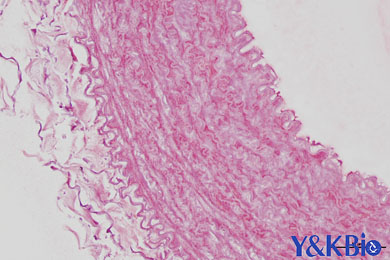

陕西依科生物技术服务有限公司致力于生物科研试剂的研发、销售及相关技术服务。从事的领域包括吉林LFB染色,吉林阿利新蓝染色,吉林普鲁士蓝染色,吉林Trap染色和其他相关病理技术服务。同时,公司还建立了独立实验室,开展Real-time PCR和Western blot等分子生物学实验及其他相关检测。

吉林LFB染色